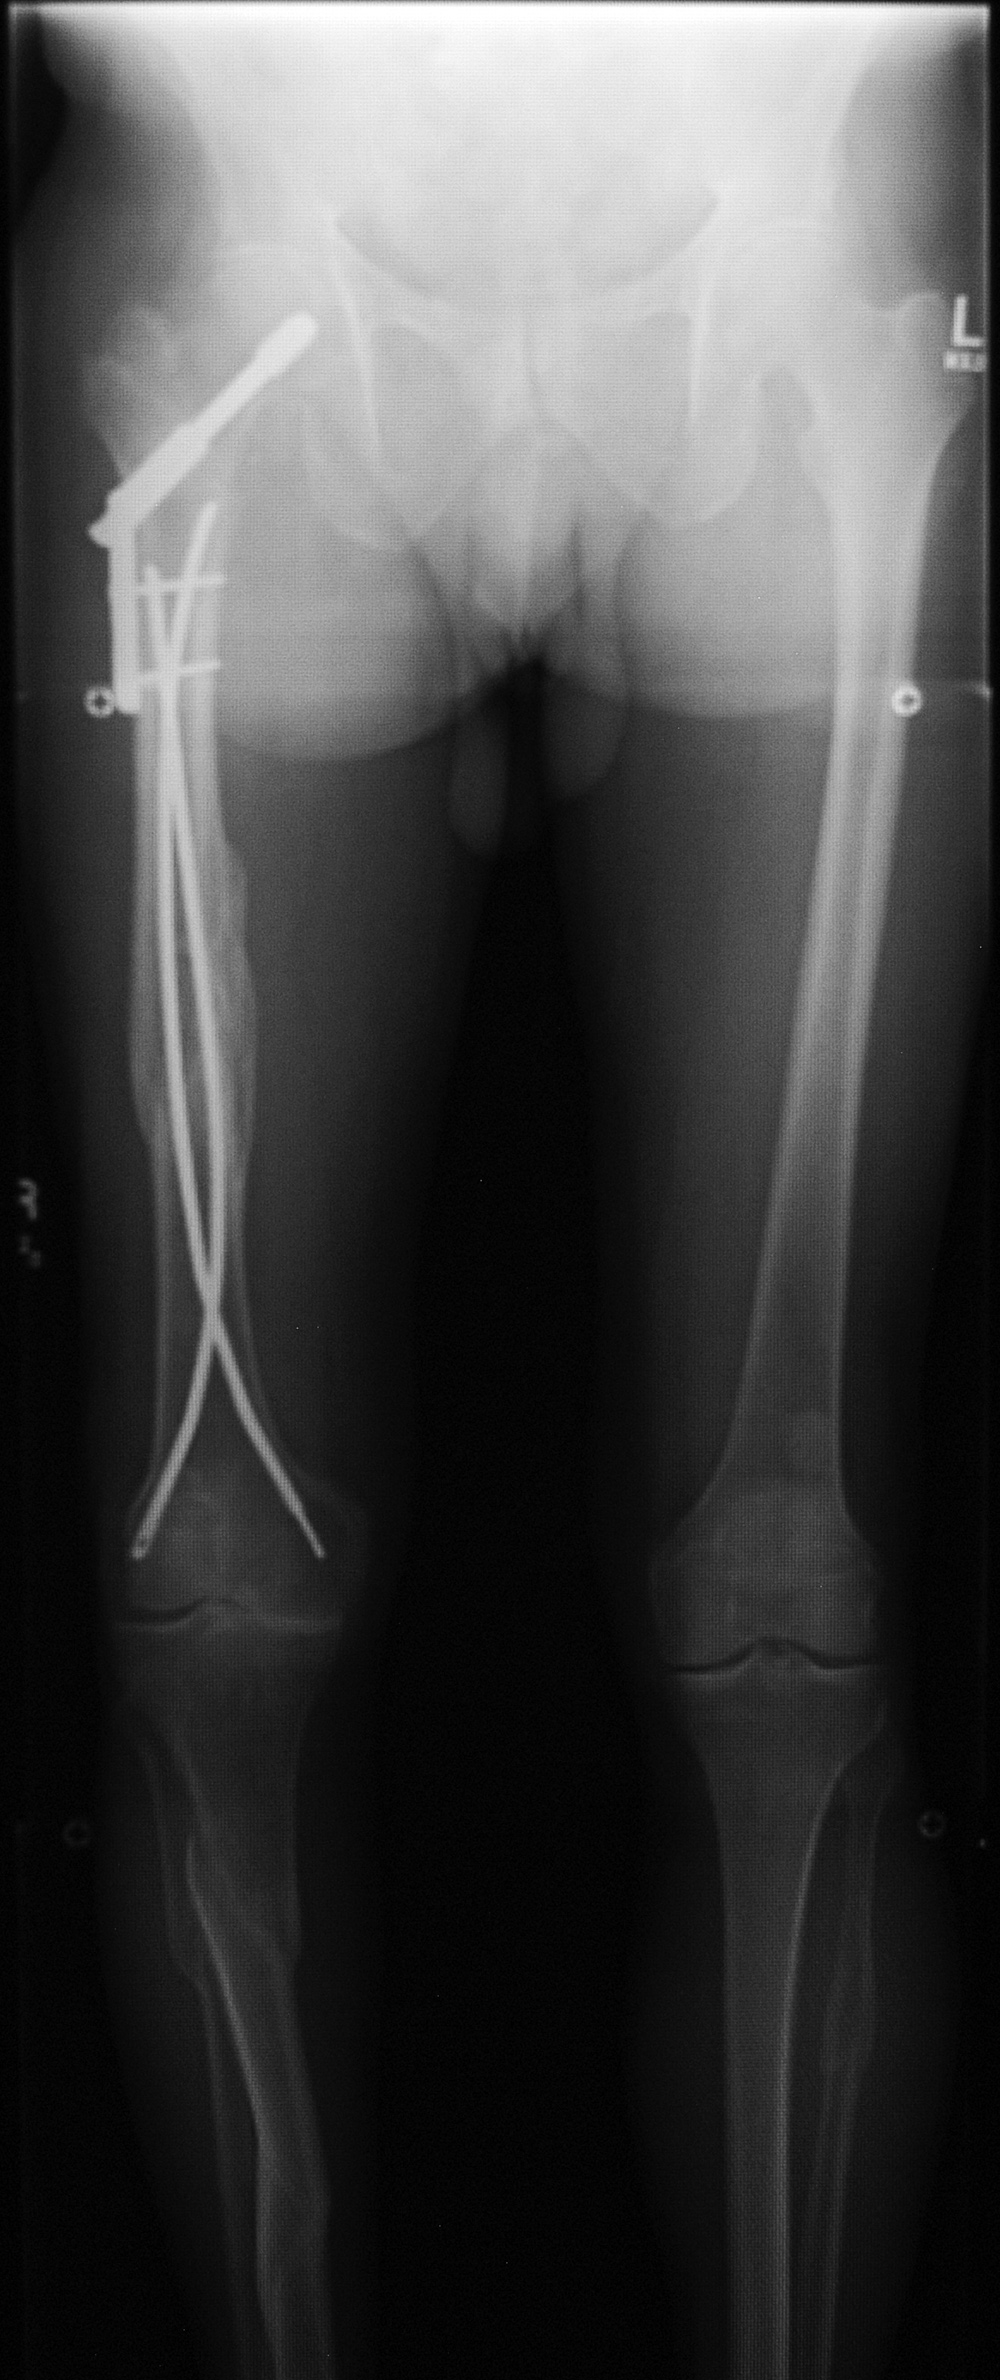

Enders (flexible) fixation nails

Flexible fixation rods

Enders (flexible) fixation rods in right femur

Enders nails

Flexible rods

Enders rods in right femur

Flexible intramedullary fixation rods stabilize a healing humerus shaft fracture. The wire in the eyelets distally (arrow) prevent the rods from backing out of the insertion portal. From Benjamin, 1994

61 year-old man with multiple old fractures. There are Enders nails (rods) in the right femur. There is also a dynamic compression screw and side plate in right hip.